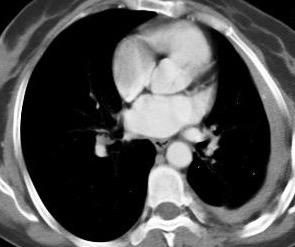

Signos radiológicos TC

Hallifax RJ et al. State-of-the-art: Radiological investigation of pleural disease Respiratory Medicine 2017

Nivel hidroaéreo o burbujas

Forma lenticular o elíptica Ángulos obtusos

> Grasa Extrapleural (60-80%)

Situación no gravitacional (no siempre)

Compresión de estructuras pulmonares

Límite muy bien definido Tabicación

Patrón ecográfico de empiema

Empiema

El derrame paraneumónico se convierte en complicado en 5-10% de los casos

Engrosamiento de la pleura parietal 36/ 59 exudados (61%) 56% de D. paraneumónicos 100% de empiemas Especificidad.. 96%.

Exudado versus trasudado.

Aquino SL, et al. Pleural exudates and transudates: diagnosis with contrast-enhanced CT. Radiology 1994

Signo de la Pleura separada “Split pleural sign”

Capas pleurales de grosor uniforme realzadas por el contraste

Dr. César Pedrosa

No específico de empiema. Indica “exudado”. 68% de pacientes con empiema pleural.

Capas pleurales de grosor uniforme

Realce grasa extrapleural (30%)

> Grasa Extrapleural. (60-80%)

Kraus GJ. Split pleural sign. Radiology 2007